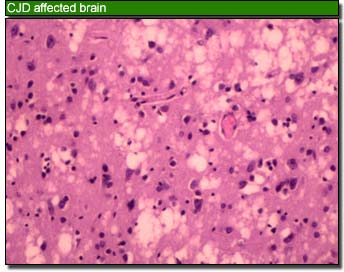

Few people today seem worried about mad cow disease (the popular name for variant Creutztfeldt Jakob Disease). In the late 1990s people spoke of vCJD like it was the new Black Death. All the newspapers, both broadsheet and tabloid, contained harrowing stories of otherwise healthy people developing symptoms that looked like a mixture of Alzheimer’s and Parkinson’s Disease. Memory loss, personality changes, and hallucinations were accompanied by impaired speech, seizures, and problems with movement. Most patients died within 6 months, often of respiratory complications. The fact that vCJD’s symptoms overlapped with so many other neurological conditions meant there was no reliable diagnostic method until a post-mortem examination of the brain could be carried out. Only then it was possible to see the tiny holes in the brain tissue caused by massive cell death (which give it a sponge-like appearance) and to test for the presence of abnormal proteins.

One of the most frightening aspects of the disease was that there was no way to be certain you did not have it. CJD appears in a number of forms: an inherited form; one that occurs spontaneously due to a genetic defect; and one transmitted through the use of contaminated surgical instruments. In the case of vCJD, the cause was thought to be ingestion of beef products infected with Bovine Spongiform Encephalopathy (hence ‘mad cow disease’). It wasn’t just people who ate meat that had reason to be worried; any food containing meat by products (such as gelatin) was a potential risk. It was a wonderful time to be vegan.

In 1997, when I was still a scientist, I did a research project at the CJD Suveillance Unit in Edinburgh- I wrote about this, and what the availability of blood tests means on the LRB Blog yesterday. It made me briefly feel like someone who actually knows something about science. No doubt, this will pass.